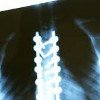

Рентген Классический метод инструментальной диагностики, исследование органов и тканей с помощью рентгеновских лучей, ведущий диагностический метод в травматологии и ортопедии. Он широко используется на этапе диагностики, определения лечебной тактики, мониторинга эффективности хирургических процедур и консервативной терапии (репозиционирование, репозиционирование, вытяжение скелета) и мониторинга отдаленных результатов лечения. Рентгенография назначается при переломах, вывихах и переломах, остеоартрозе, остеохондрозе, врожденных аномалиях, других заболеваниях и патологических состояниях.

Современную травматологию и ортопедию невозможно представить без рентгенологического исследования. Рентген был и остается наиболее распространенным и наиболее информативным методом диагностики повреждений и заболеваний опорно-двигательного аппарата. В 1895 году немецкий физик Вильгельм Конрад Рентген обнаружил, что рентгеновские лучи по-разному поглощаются тканями различной плотности, и, проходя через тело человека, оставляют изображение внутренних органов на специальной пленке. На основании этого изображения врач может определить местоположение, форму, размер и структуру органа, определить патологические изменения, оценить их тяжесть и поставить диагноз заболевания или травмы.

Рентгеновские снимки четко показывают границы и структуру легких, что позволяет использовать рентгеновские лучи в больших масштабах для выявления осложнений переломов ребер (гемоторакс, пневмоторакс). Рентгенологические исследования проводятся не только во время первоначальной диагностики травм и нарушений скелета. Повторные рентгенологические исследования во время лечения дают возможность оценить качество снижения, степень адгезии перелома и эффективность консервативного или хирургического лечения.